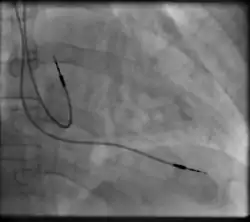

Transvenous pacing, when used for temporary pacing, is an alternative to transcutaneous pacing. A pacemaker wire is placed into a vein, under sterile conditions, and then passed into either the right atrium or right ventricle. The pacing wire is then connected to an external pacemaker outside the body. Transvenous pacing is often used as a bridge to permanent pacemaker placement. It can be kept in place until a permanent pacemaker is implanted or until there is no longer a need for a pacemaker and then it is removed.

Right atrial and right ventricular leads as visualized under x-ray during a pacemaker implant procedure. The atrial lead is the curved one making a U shape in the upper left part of the figure.